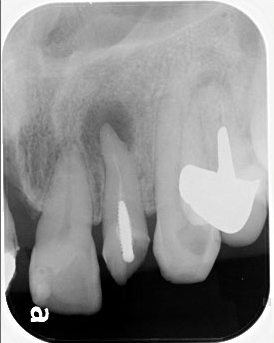

右上の奥から2番目の歯の神経が感染していたので、神経を取り、最終的な薬で埋めたところです。

この後、この歯はブリッジの土台の歯になります。